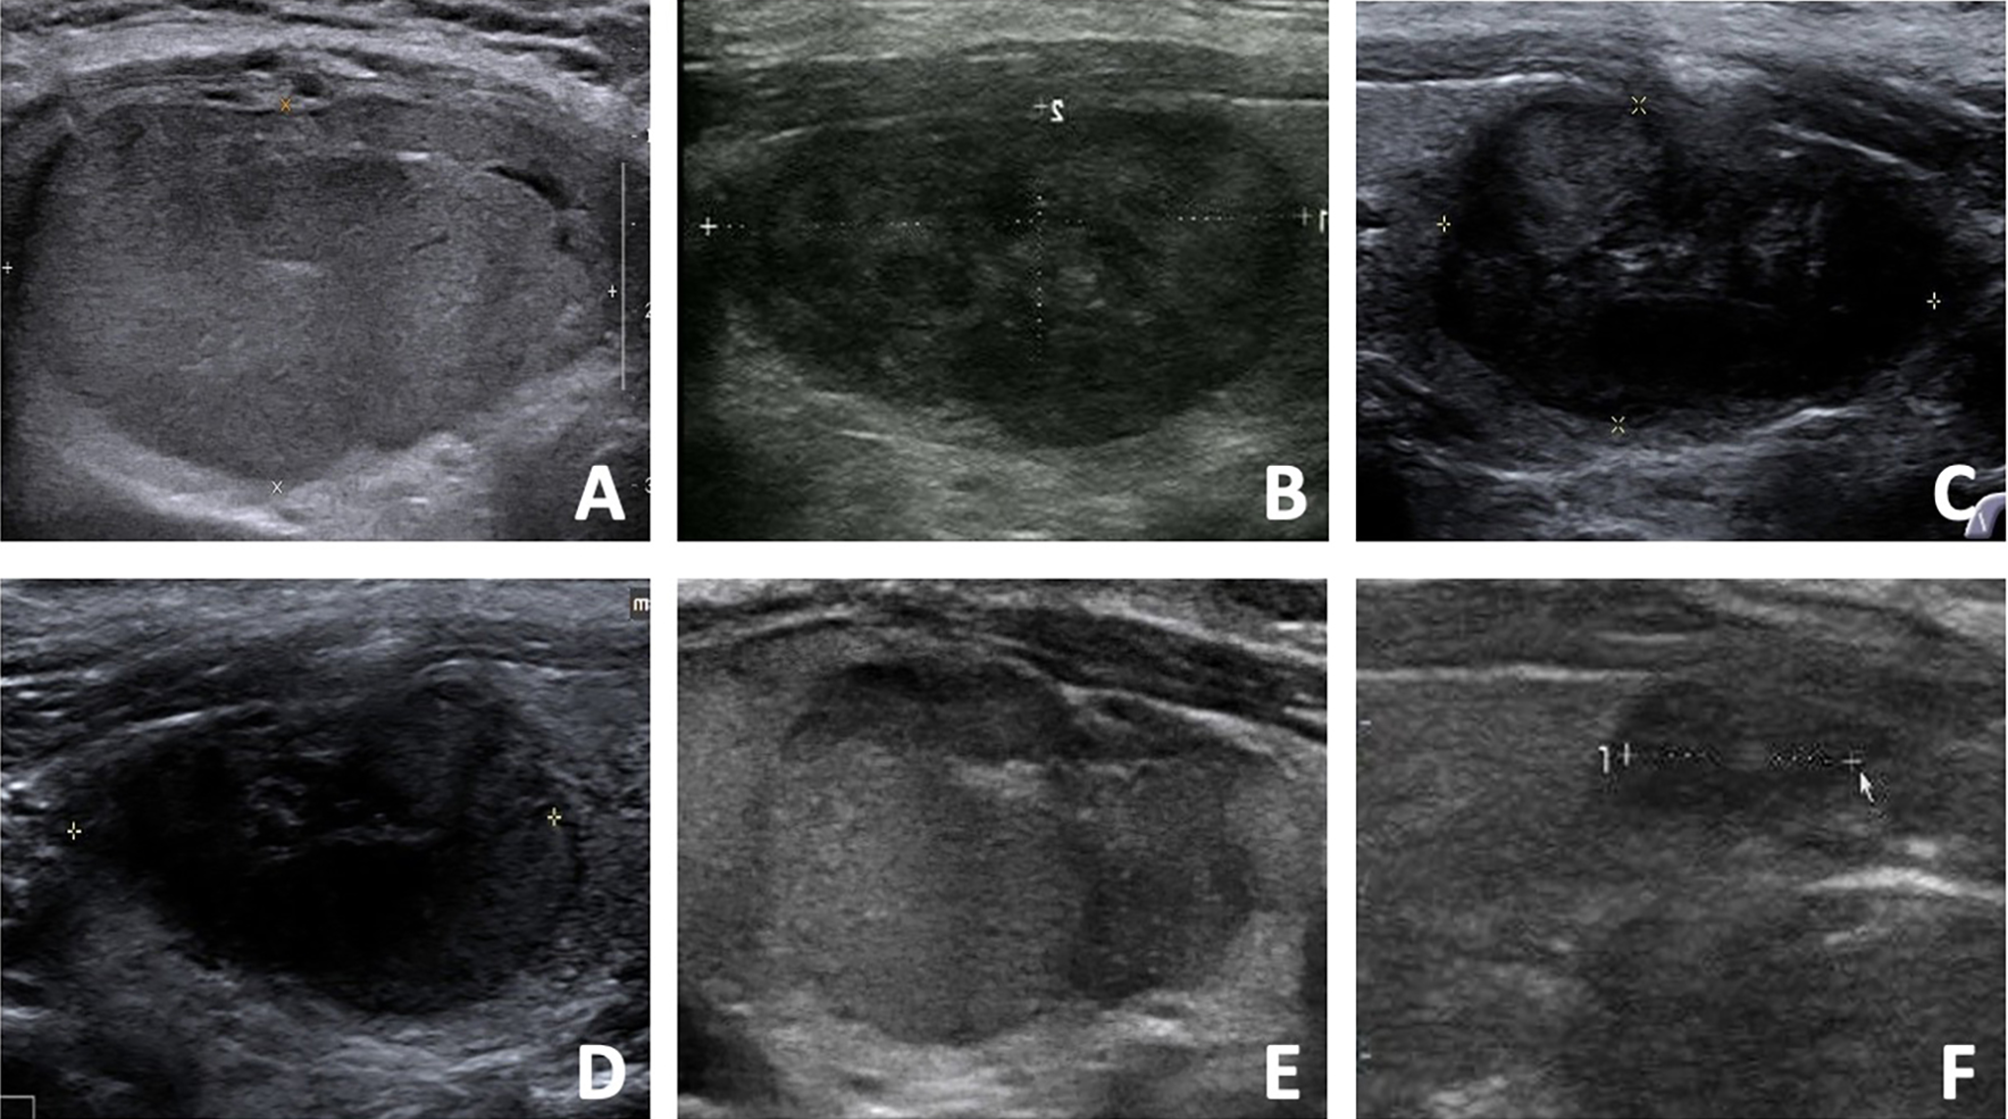

Regrowth was observed in 30 out 220 nodules (13.64%), which all occurred in the untreated peripheral area. The mean timing of regrowth was at 22.40 ± 12.10 months after RFA. All the regrowth nodules underwent additional RFA. The changes of volume and VRR in the two groups are present in Table 2. In the first 12 months, VRR in the two groups were nonsignificant (all P >0.05). However, at 24 months after RFA, VRR in the non-regrowth group were significantly larger than that in the regrowth group (90.39 ± 11.23% vs 78.65 ± 12.24%, P = 0.002) (Figure 1). A total of 7 nodules had volume reduction less than 50% at 12 months. Five nodules were in the regrowth group and 2 in the non-regrowth group (16.67% vs 1.05%, P <0.001). Representative cases in the two groups are shown in Figures 2, 3.

Figure 2 The US images of a 48- year-old male with a benign thyroid nodule in the regrowth group. (A) The initial volume of nodule was 22.27 ml before RFA. The nodule was located in the dangerous location, and the vascularity was grade 4. The risk of regrowth by the nomogram was 67%. (B) At 1 month after RFA, the volume was 5.28 ml and VRR was 76.29%. (C) At 3 months after RFA, the volume was 3.48 ml and VRR was 84.37%. (D) At 6 months after RFA, the volume was 2.89 ml and VRR was 87.02%. (E) At 12 months after RFA, the US showed nodule regrowth and the volume was 4.34 ml and VRR was 80.51%. Additional RFA was performed. (F) At 6 months after additional RFA, the volume was 1.65 ml and VRR was 92.59%.